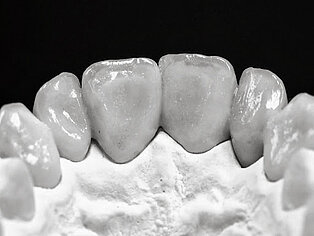

Keramikstufen

Meisterarbeit von Peter Dengel

Vom Langzeitprovisorium zur TEK 1 Arbeit